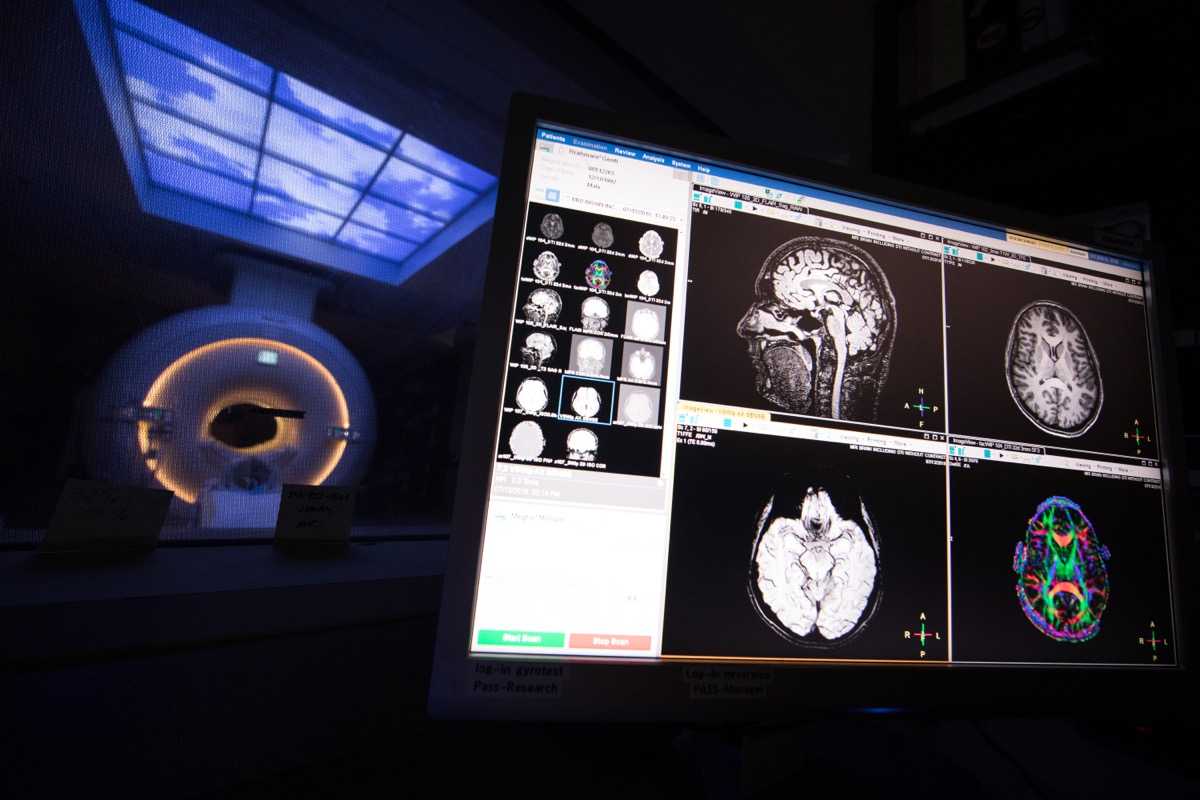

Moses Campus, along with Children’s Hospital at Montefiore Einstein, features 726 adult inpatient beds and 106 pediatric inpatient beds. The facility also offers services to outpatients. As an NCI-Designated Cancer Center, Moses provides diagnostic and therapeutic modalities through an active theranostics program. While training at Moses, residents partake in a particularly rigorous program in oncologic and non-oncologic pediatric and adult nuclear medicine. Our Transplant Center, also on-site, affords residents the ability to evaluate organ physiology pre- and post-transplant.